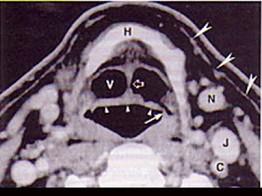

男,55岁,声嘶6年,有长期吸烟史。检查:无呼吸困难。喉镜检查:声带慢性充血,可见右侧声带可见菜花样新生物,右侧声带活动固定,喉部CT检查如下图:诊断...

问题 男,55岁,声嘶6年,有长期吸烟史。检查:无呼吸困难。喉镜检查:声带慢性充血,可见右侧声带可见菜花样新生物,右侧声带活动固定,喉部CT检查如下图: 诊断首先考虑 ( )

选项 A、喉乳头状瘤 B、喉结核 C、慢性喉炎 D、喉癌 E、声带白斑

答案 D